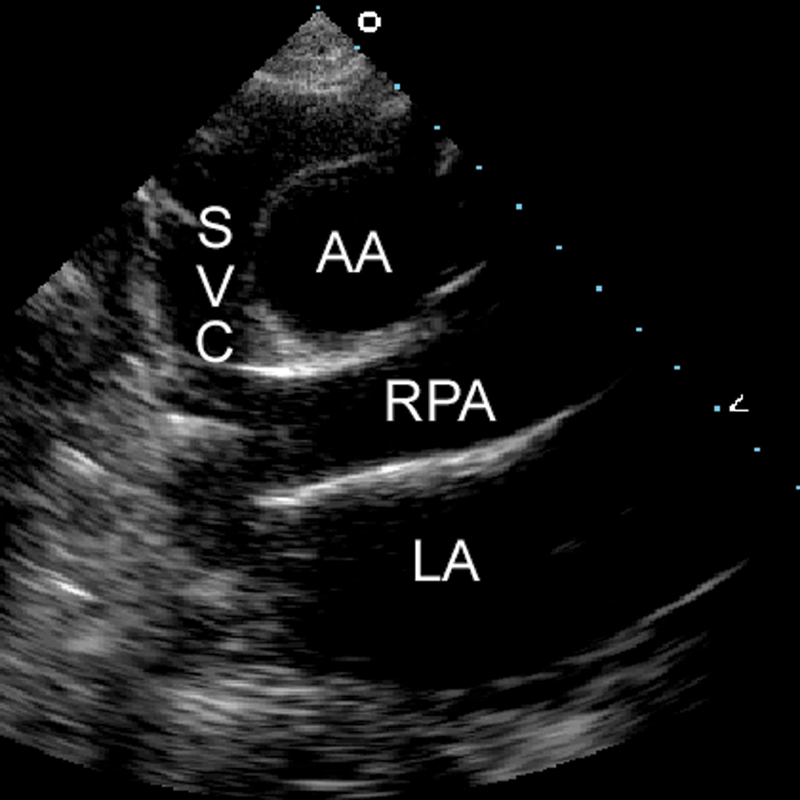

فحوصات تشخيصية لبعض امراض القلب والشرايين التاجية